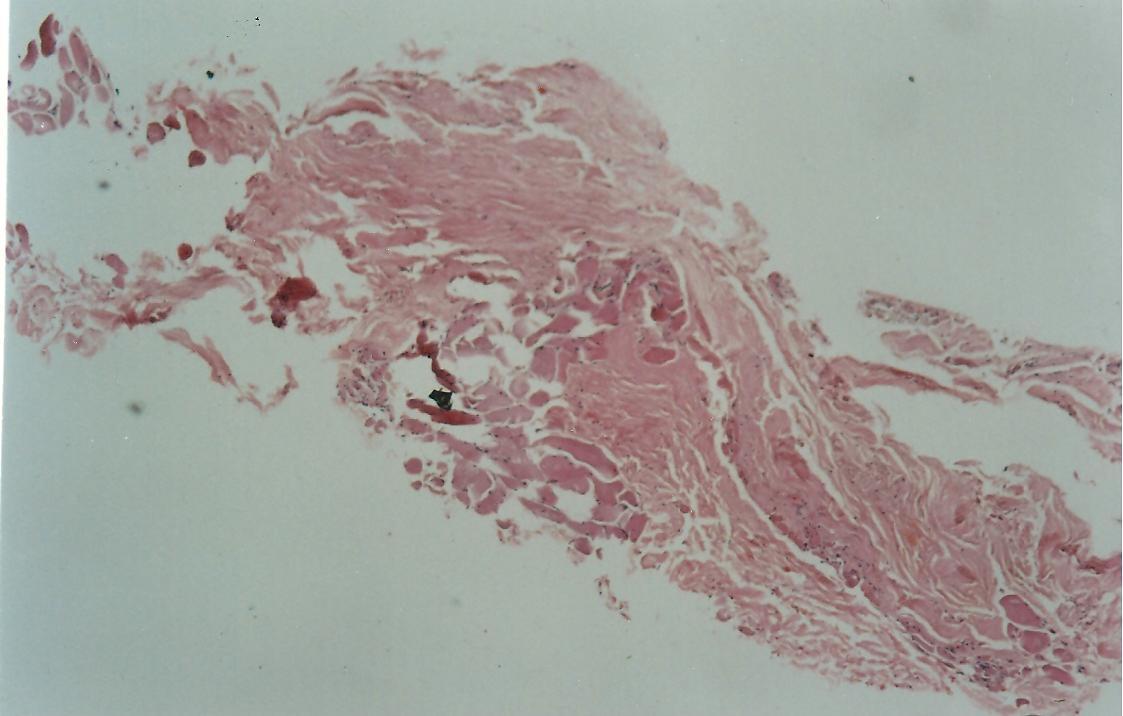

The medial side of the TMF graft is attached to the temporalis muscle after harvesting the graft, the muscle fibres were scraped of the graft. This part of the graft is still rough as compared to the lateral side which is shiny and smooth on microscopic examination. (Figure-1) Before placing the graft it was moistened with saline. In forty one patient technique I was used and in thirty nine patient, technique II was applied.

Figure-1.Fig x40, HE: Shows skeletal muscle on lower left and fibrocollagenous tissue of fascia on upper right

Fig x40, HE: Shows skeletal muscle on lower left and fibrocollagenous tissue of fascia on upper right